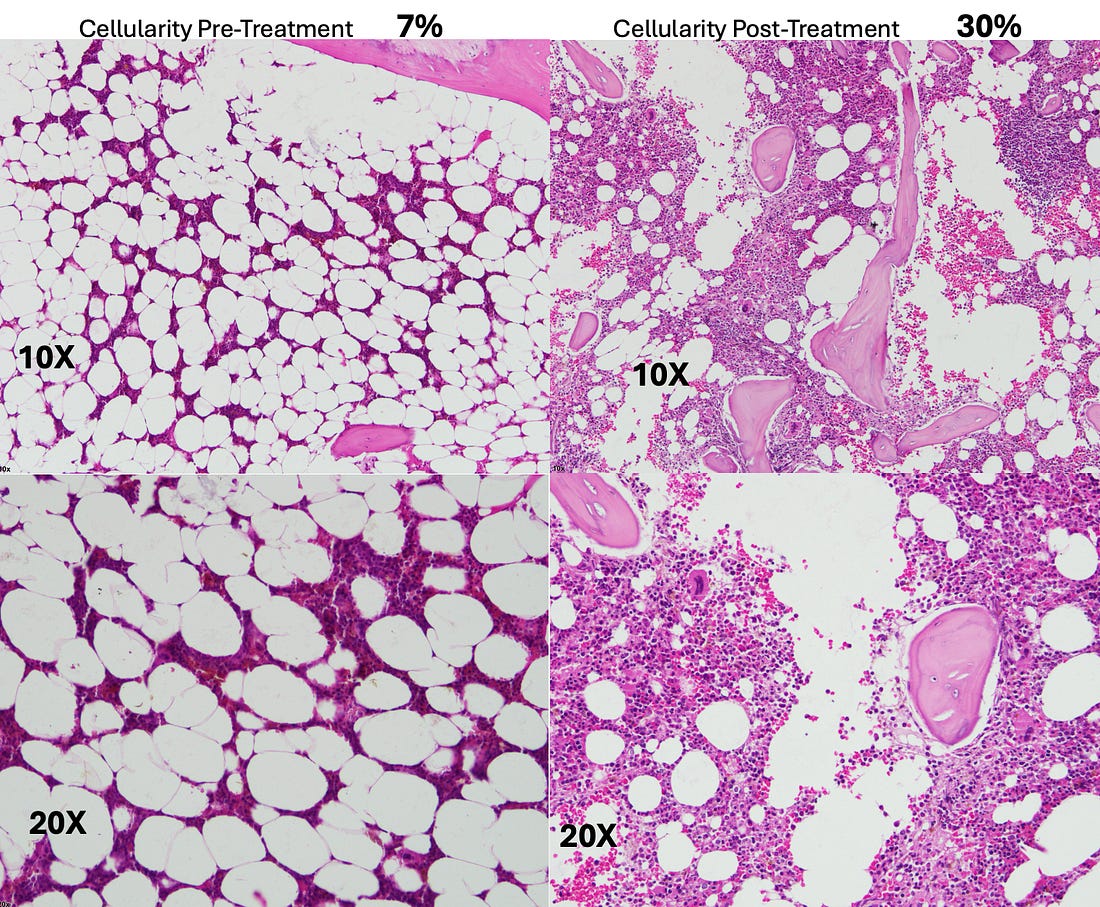

advice). •He felt very strongly about the necessity of chelation therapy in cancer (e.g., to prevent subsequent heart attacks following successful D-hematoxylin treatments—which occurred years later in some of Tucker’s cases) and to that you should not give leukemia patients with anemia iron as the cancer needed that to grow (to the point he would sometimes also chelate iron in leukemic patients). •McCann was also very focused on cultivating bacteria on a target media that would dissolve specific biological targets (e.g., he cultured bacteria from a dead cow’s cataract and then found it could eliminate other cataracts; likewise, he found this approach worked for cancer). Note: my experience with individuals like McCann is that some of their insights are spot on while others they have a deep conviction in are ultimately not correct. The Next PhaseLike many alternative therapies, D-hematoxylin grew up in “the Wild West” of alternative medicine. This was made possible by its very low toxicity profile, which allowed it to be used in humans at widely varying doses without significant side effects. Fortunately, the threads keeping D-hematoxylin from being lost eventually converged in Ecuador with a doctor who’d successfully treated 44 out of 45 cases of microbiologically confirmed chronic bacterial prostatitis using DMSO combined with antibiotics that were applied directly into the bladder (much in the same DMSO is FDA approved to treat interstitial cystitis) who then tested negative for any infection 15-20 days following treatment (with no subsequent recurrences), demonstrating DMSO's ability to counteract bacterial resistance. Note: interestingly, Stanley Jacob, was still alive when these treatments were initiated (he died in 2019 at age 91). At the start of the prostatitis treatments, the doctor in Ecuador contacted him for advice, and Jacob encouraged the experiment, agreeing it was a good idea, even though he hadn't heard of anyone attempting it before. As he’d heard of McCann through Ecuador’s medical community, these prostatitis successes inspired that doctor to try intravesical DMSO mixed with hematoxylin for a prostate cancer patient (which was administered in the same manner and frequency as his prostatitis treatments). This worked, and he gradually began using it for other prostate cancer patients and then other cancers as well, which gradually grew into a fifteen-year research project on the therapy (which he's shared with me over the course of a few months). Note: I also know of one individual who used D-hematoxylin intrarectally over a prolonged period to locally treat a cancer there, but the data on this approach is still limited. Recent D-Hematoxylin PatientsThat

project involved treating approximately 85 patients, with the cure rate

in patients who had not previously received chemotherapy averaging

between 80-90%. As such D-hematoxylin is an excellent cancer treatment

but it is not perfect and will not work for everyone. •Leukemias (particularly acute leukemia) Note: myeloproliferative neoplasms (e.g., polycythemia vera, essential thrombocythemia and primary myelofibrosis) depend upon a mutant protein for survival which was shown to be susceptible to disruption by a few small compounds including hematoxylin. While D-hematoxylin has not been tested on these disorders, this study (along with the other known effects of DMSO and D-hematoxylin) suggest it could be an effective treatment for them. The cancers with a poorer response included: •“Solid” tumors Additionally, if there is a cancer marker associated with the tumor (e.g., CEA or PSA), it will often rapidly drop, making it very easy to track the progress of D-hematoxylin. As the following cases show, many of the improvements were quite profound: •A 54-year-old female patient with Classic Hodgkin Lymphoma which had invaded 72% of her bone marrow, with CD20-positive expression. She had a variety of symptoms (e.g., recurrent pleural effusions and anemia), but since her religion did not permit blood transfusions, she received only D-hematoxylin and EDTA and then had a full recovery (with no recurrence in twelve years of follow up). The most striking aspect of this case was the change in her bone marrow biopsy, after three months of treatment with D-hematoxylin (unlike chemotherapy) it selectively destroyed the cancerous cells, allowing normal ones to regrow and rapidly addressed her anemia. •A 72 year old patient with leukemia who was anemic and had her anemia rapidly improve following D-hematoxylin: Likewise, similar bone marrow changes were seen in her. Note: another similar leukemic patient on D-hematoxylin with anemia had no improvement. After investigating, it was determined this was due to her regularly using WD40 on a daily basis (without respiratory protection) and hence having a bone marrow intoxication which was directly damaging the bone marrow (and in turn the leukemia diagnosis may have been incorrect). •A 16 year old male with a mediastinal seminoma that received 16 D-hematoxylin infusions, 5 IV vitamin C infusions and then one chemotherapy session (on July 7) where cisplatin and bleomycin were combined with DMSO (after which he continued chemotherapy and has recovered from the cancer). •A 63-year-old male with cholangiocarcinoma (a rare, aggressive and notoriously difficult to treat cancer of the bile duct) who received D-hematoxylin plus chelation and vitamin C (but no chemotherapy). During his successful treatment, a drain from his bile duct was also monitored for tumor markers. Additionally, the cancer debris could be seen in the drainage tube (an internal-external percutaneous transhepatic biliary drainage catheter)—something which the Ecuador doctors now view as essential to have if D-hematoxylin will be used in this cancer: Note: another bile duct cancer patient (a 68 year old female) received palliative D-hematoxylin while waiting for surgery and chemotherapy (which ultimately could not be done because of how advanced the cancer was). Her cancer markers levels significantly improved following D-hematoxylin (and continued to reduce during gaps in treatment), but she eventually lost the will to live and passed after 16 months. •A 63-year-old man with B-cell lymphoproliferative disorder who received D-hematoxylin for 10 days (with no other treatment), experienced a significant drop (normalization) of his white blood cell count during that time then stopped at the advice of his hematologists, and two years later died from COVID. •A man who had a stable bladder polyp which became cancerous following a covid vaccination (with the initial sign being a large blood clot in the urine) which when examined had spread in a large portion of the urinary tract’s endothelium. It was surgically removed, but due to how far it had spread, the urologist told the patient he would only survive for two months. They then began five weeks of intravesical and IV D-hematoxylin, and in four years, the cancer never returned (which led to the urologist telling everyone about the “amazing” surgical procedure they had performed). •A 55-year-old female who had a mediastinal tumor (type unknown as it was wrapped 560° around the aorta and hence could not be biopsied) which fully resolved after 33 daily D-hematoxylin treatments. Additionally, this was the CT prior to treatment where the tumor can be seen around the aorta: While this was the CT two weeks following the D-hematoxylin treatment: Lastly, at five years follow up, there was no recurrence. •A 27-year-old female with acute lymphoblastic leukemia reacted poorly to two sessions of chemo, was classified as terminal, and then was started on D-hematoxylin. She had a significant improvement in her cancer and simultaneous improvement in her anemia which continued long after conventional treatments for anemia were halted (which did not include blood transfusions as she was a Jehovah’s Witness). In a before (1-2-2020) and after (2-1-2020) video I saw of this patient, she initially looked very frail and had difficulty walking, while just a month later (after 31 days of treatment), she had no difficulty walking and looked vibrant and robust. Additionally, they continued to monitor her on a monthly basis, and four years later, she’d had a healthy baby, and had her hematocrit range from 42 to 48 (which is slightly above average) indicating she had no further risk of anemia (even though hematologists in the hospital had predicted her reckless pregnancy would cause severe anemia). Additionally, her ESR (which had been significantly elevated prior to treatment) normalized (and remains normal 5 years later). Lessons from EcuadorIn addition to observing a remarkable degree of success from D-hematoxylin, the Ecuadorian team was able to discern a variety of patterns (many of which mirrored Tucker’s previous observations) that helped craft their treatment protocols. For example: •While DMSO alone can somewhat help with cancer, the effects of DMSO combined with hematoxylin are completely different from what would be observed with DMSO alone. •They saw many signs during their treatment protocols that D-hematoxylin selectively targeted cancer cells. •Cancers did not develop resistance to D-hematoxylin (which is a common challenge with many chemotherapies). •While some tumors rapidly disappear, other types frequently become avascular (which stops their growth) and dried-out, blanched, or fibrous rather than being directly shrunk (e.g., I reviewed cases where a brain cancer simply stopped growing). In many cases, those tumors are then very easy to extract surgically. Note: to my knowledge, everyone besides that Ecuadorian team who treats with D-hematoxylin still uses Tucker’s protocol and has not tried to improve upon it. Variations in D-Hematoxylin EfficacyOn

D-hematoxylin is given to anemic patients with leukemia, their red

blood cell counts will often rapidly improve, suggesting DMSO is either

differentiating leukemic cells into ones that can produce red blood

cells or providing the space for healthy bone marrow cells to begin

producing red blood cells. For this reason (and McCann’s view that

supplemental iron was unwise in leukemia), the doctor has explored

treating anemia from leukemia with D-hematoxylin and found it works

better than iron. •While D-hematoxylin is safe, it is important to titrate the dose, as if the dose is too high, patients can experience chills, fevers or shortness of breath. Since the “high” dose varied from patient to patient (or even sometimes for the same patient), the doctor needs to carefully monitor them during treatment and typically the infusion is continued until the patient starts feeling hot or cold. Additionally, hot-cold alternating sensations often occur during the first two sessions, while from the third on, chills are often experienced—all of which can require a doctor to walk the patient and their family through what is occurring so there is no cause for concern (particularly since the chills while harmless can be quite concerning)—which again touches upon how important patients communication is when administering this therapy. Note: from looking through all of this data, I am relatively sure much higher (and likely even more effective) doses could have been used but were not because they were not willing to risk any possible adverse effects from the therapy (whereas in contrast chemotherapy is routinely given at doses which create significant toxicity and reactions). Chemotherapy and RadiationSince cancers are often treated in combination with conventional therapies, they also monitored how D-hematoxylin interacted with them, discovering: •There were no issues combining D-hematoxylin with radiation therapy. •Patients who had already been treated with cytotoxic chemotherapies by the time they received D-hematoxylin tended to have a much poorer response to D-hematoxylin. However, if cytotoxic chemotherapy was started at least three weeks after they’d initiated D-hematoxylin, they were much more likely to have a successful cancer treatment. •In more difficult cases (e.g., D-hematoxylin was started too late and they’d already had significant chemotherapy), like the DMSO-NaHCO₃ studies, D-hematoxylin was not curative but rather significantly decreased their pain and improved their remaining quality of life. How Does D-Hematoxylin Work?In the first half of this series, I compiled the extensive volume of literature which elucidated the mechanisms behind many of DMSO’s anticancer properties. However, while compelling, those mechanisms are not sufficient to explain why this mixture is so effective in treating cancer (particularly since D-hematoxylin’s rapid elimination of cancers is not observed with DMSO alone). Note: when D-hematoxylin is placed into the blood, it will rapidly change color, suggesting hematein (oxidized hematoxylin) is the active agent. Further strengthening this observation, when hematoxylin was sterilized by the Ecuador team through exposing it to ozone (a powerful oxidizing agent), prior to being mixed with DMSO and then infused, D-hematoxylin’s efficacy is not impaired (however exposing powdered hematoxylin to ozone did not evidently change its color so it’s unlikely ozone exposure fully oxidizes it). Since no definitive mechanism for D-hematoxylin exists, there are a large number of possible explanations for why D-hematoxylin destroys cancer, and presently, my best guess is that for some reason, D-hematoxylin has a high affinity for cancerous DNA and either due to its persistence around the cancerous DNA or it having a specific toxicity to cancerous DNA then destroys it (which in turn eventually eliminating the tumor). However, in many cases, the damage to the nucleus of cancer cells is gradual rather than immediate, so rather than being directly toxic to cancer DNA, once there, D-hematoxylin may initiate some type of process which eventually destroys the cancer’s DNA. Furthermore, while D-hematoxylin will travel to cancers and then eliminate them, it is not effective if put directly into a cancer, which again implies a non-standard form of toxicity is occurring. That said, I am not sure why that affinity for cancers exists or why D-hematoxylin neither harms normal cells nor even stays in them. Note: when hematoxylin is bound to a metal salt, it (and hematein) becomes able to bind to and hence stain DNA (which is why most commercial hematoxylin are combined with an often toxic metal). DMSO likely imparts that ability to hematoxylin as well, although it does so through a different mechanism than the mordants (which are simply positively charged metals that bridge negatively charged molecules (e.g., hematein and DNA) together. Thomas RogersAfter Tucker began having success in human patients, a graduate student, Thomas D. Rogers, saw the importance of figuring that question out and thus decided to conduct his dissertation on the effects of D-hematoxylin on tumors (which can be viewed here and has many pictures of cancers affected by D-hematoxylin).